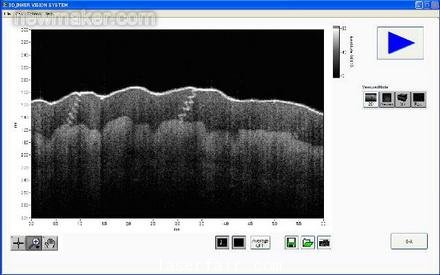

我們的系統(tǒng)現(xiàn)在可以更快地顯示物體(包括人體器官和其他移動(dòng)的樣品)的圖像。而且,新的基于FPGA的系統(tǒng)可以提供實(shí)時(shí)測(cè)量信號(hào)處理,通過消除測(cè)量和顯示之間的延遲,提高顯示性能。圖4表示成像系統(tǒng)的LabVIEW面板。

newmaker.com

圖4. SS- OCT成像系統(tǒng)的面板